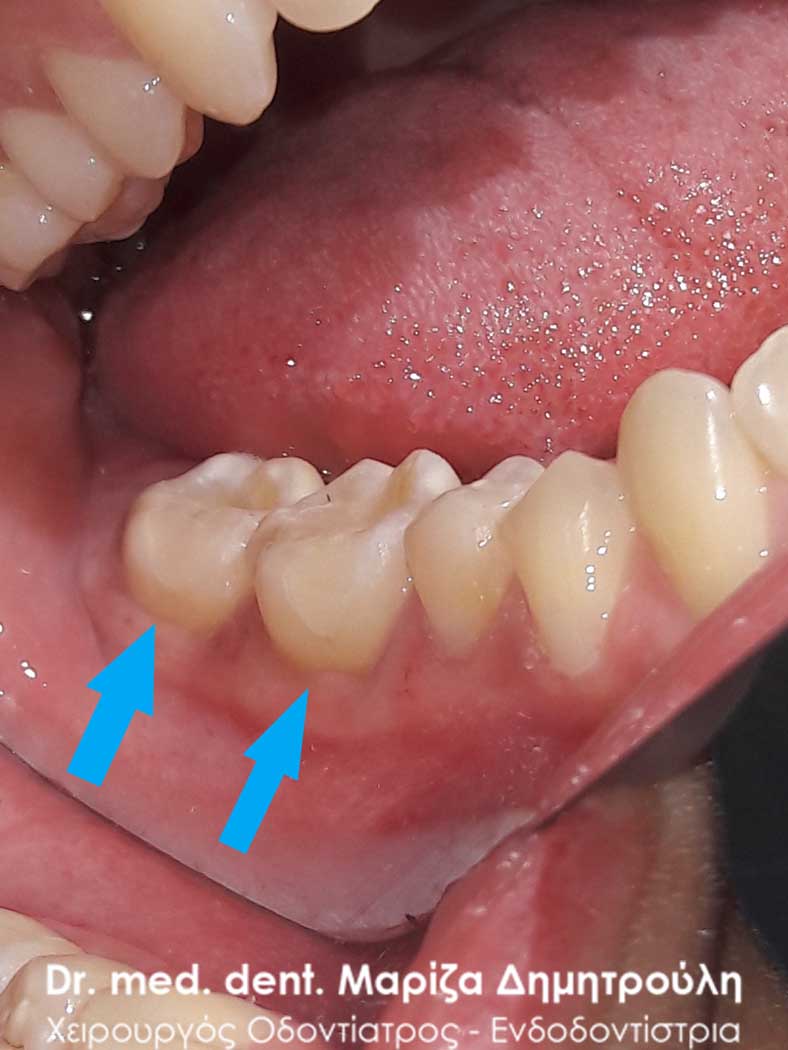

Η ασθενής είχε αντικαταστήσει πριν 2 μήνες 2 σφραγίσματα ( στον 1ο γομφίο και στον 1ο προγόμφιο) στην αριστερή πλευρά της άνω γνάθου. Ανέφερε οτι από τη στιγμή εκείνη υποφέρει από έντονους πόνους. Μετά την κλινική εξέταση διαπιστώθηκε η παρουσία τερηδόνας στο 2ο γομφίο και στο φρονιμίτη. Αποφασίστηκε η αποκατάσταση των τερηδονισμένων δοντιών με λευκά σφραγίσματα σύνθετης ρητίνης. Όσον αφορά τα δόντια με την ευαισθησία πραγματοποιήθηκε αντικατάσταση τους με προσωρινό καταπραυντικό υλικό σφραγίσματος. Σε επόμενο ραντεβού πραγματοποιήθηκε η τελική αποκατάσταση των δοντιών αυτών με λευκά σφραγίσματα ρητίνης.

ΠΡΙΝ

META